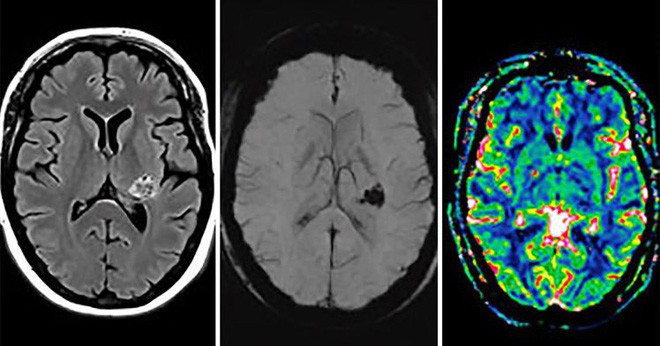

Một người phụ nữ cho biết cô nghe được những lời nói siêu nhiên. Bác sĩ đã chụp cắt lớp não của người phụ nữ này. Không ai còn dám nói cô bị cho là tâm thần sau khi xem kết quả.

Một người phụ nữ tin rằng mình có thể nghe và nói chuyện được với Chúa trời, thậm chí sau khi nghe những âm thanh đó, cô bắt đầu có hành động tự làm tổn thương cơ thể mình.

Người phụ nữ không rõ danh tính đã khiến các nhà nghiên cứu tại trường đại học Bern, Thụy Sĩ chú ý. Ban đầu họ nghĩ rằng có thể cô mắc phải chứng bệnh tâm thần tuy nhiên quan sát biểu hiện của bệnh nhân, họ bỗng cảm thấy có điều bất thường và tin rằng chắc hẳn phải có điều gì tiềm ẩn phía sau.

Sau khi tiến hành chụp cắt lớp cho bệnh nhân, quả thật suy đoán của họ không hề sai. Bên trong não của người phụ nữ này phát hiện có một khối u đang phát triển. Giáo sư tâm thần và thần kinh học Sebastian Walther cho biết: “Khối u nằm trên khu vực mạng lưới thần kinh quan trọng ảnh hưởng đến nhận thức về giọng nói. Vì vậy bệnh nhân đã nghe được những ảo thanh, và khiến cho cô tin rằng mình đang nói chuyện với Chúa”.

Cộng thêm với niềm tin tôn giáo mạnh mẽ, người phụ nữ này dần dà đã phải đối mặt với sự ảo tưởng nghiêm trọng. Khối u được xác định phát triển ở vùng dưới đồi, phần lớn nhất của vùng não trung gian, gây ra các biểu hiện tương tự như bệnh nhân mắc phải chứng tâm thần phân liệt.

Hiện tượng nghe được ảo thanh bao gồm những tiếng thóa mạ, giọng nói xuất hiện trong não giống như đang nói chuyện với một thế lực siêu nhiên nào đó là một trong những biểu hiện khá phổ biến của những người gặp vấn đề thần kinh.

Các nhà nghiên cứu, những người đã dành nhiều năm tìm hiểu về bệnh tâm thần phân liệt, tin rằng trường hợp của bệnh nhân này sẽ giúp cho họ có thể hiểu rõ hơn về tình trạng này. Họ cho biết, đây là bằng chứng cho thấy các triệu chứng tâm thần phân liệt không được kích hoạt trên toàn bộ não mà là sự gián đoạn cụ thể ở một số khu vực nào đó.